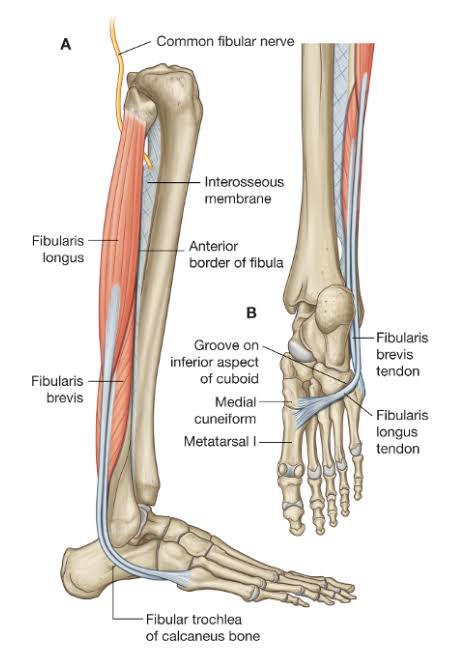

- consequential damage from my Achilles separation (March 2018) to my peroneus longus and brevis tendons keeping me off the bike. Even walking was painful

After an extended and painful recovery from the Achilles, I was avoiding surgery and was crossing fingers that the peroneus tendons would miraculously sort themselves out. But three years later they were, if anything, worsening.

April 2023 – a well recommended orthopod lopped off and removed a section of the damaged longus and repaired the damaged brevis. And for good measure lopped a wedge out of my heel bone (calcanus) to straighten up the heel bone to reduce the pressure on the peroneus tendons. Or rather, the remaining peroneus tendon. For those with any medical leaning – a Dwyer osteotomy.

The point of that detour was that I clearly had a top notch orthopedic specialist. He optimized my original design and had a left over bit of superfluous tendon after the op!

I did search for a photo of a healthy tendon, but Google didn’t oblige.